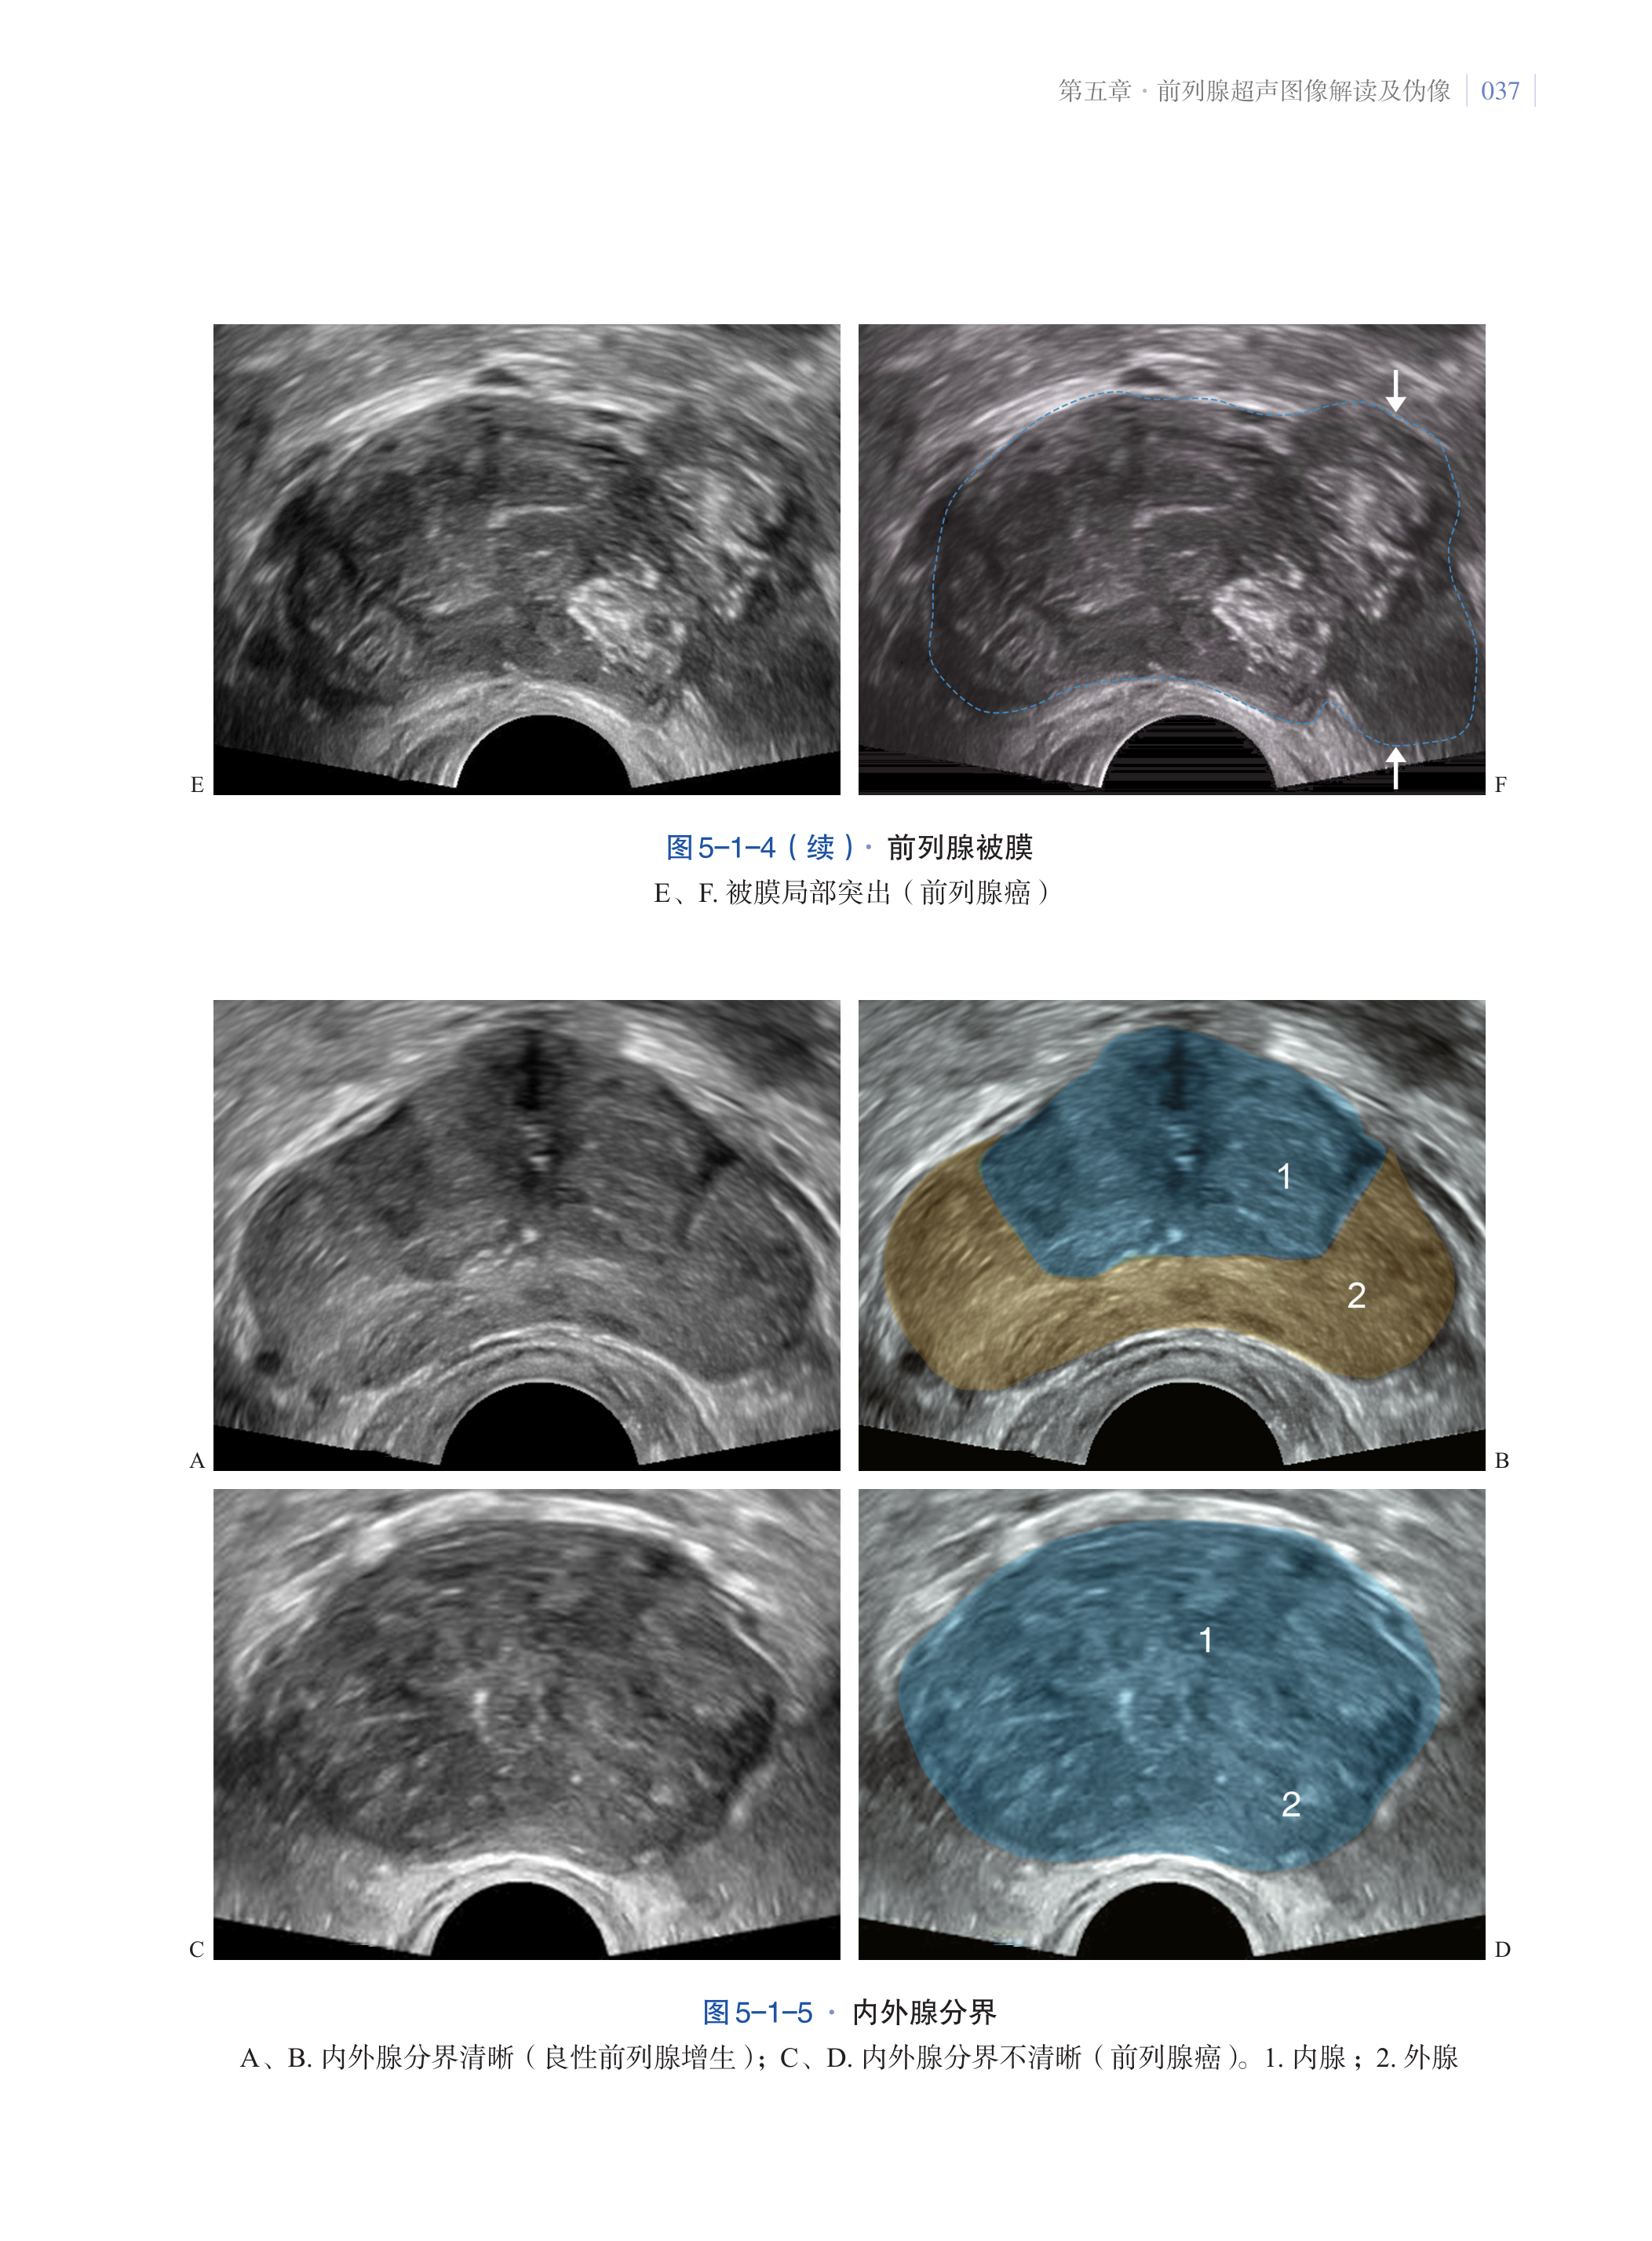

第五章·前列腺超声图像解读及伪像 033

第一节·前列腺超声图像解读 033